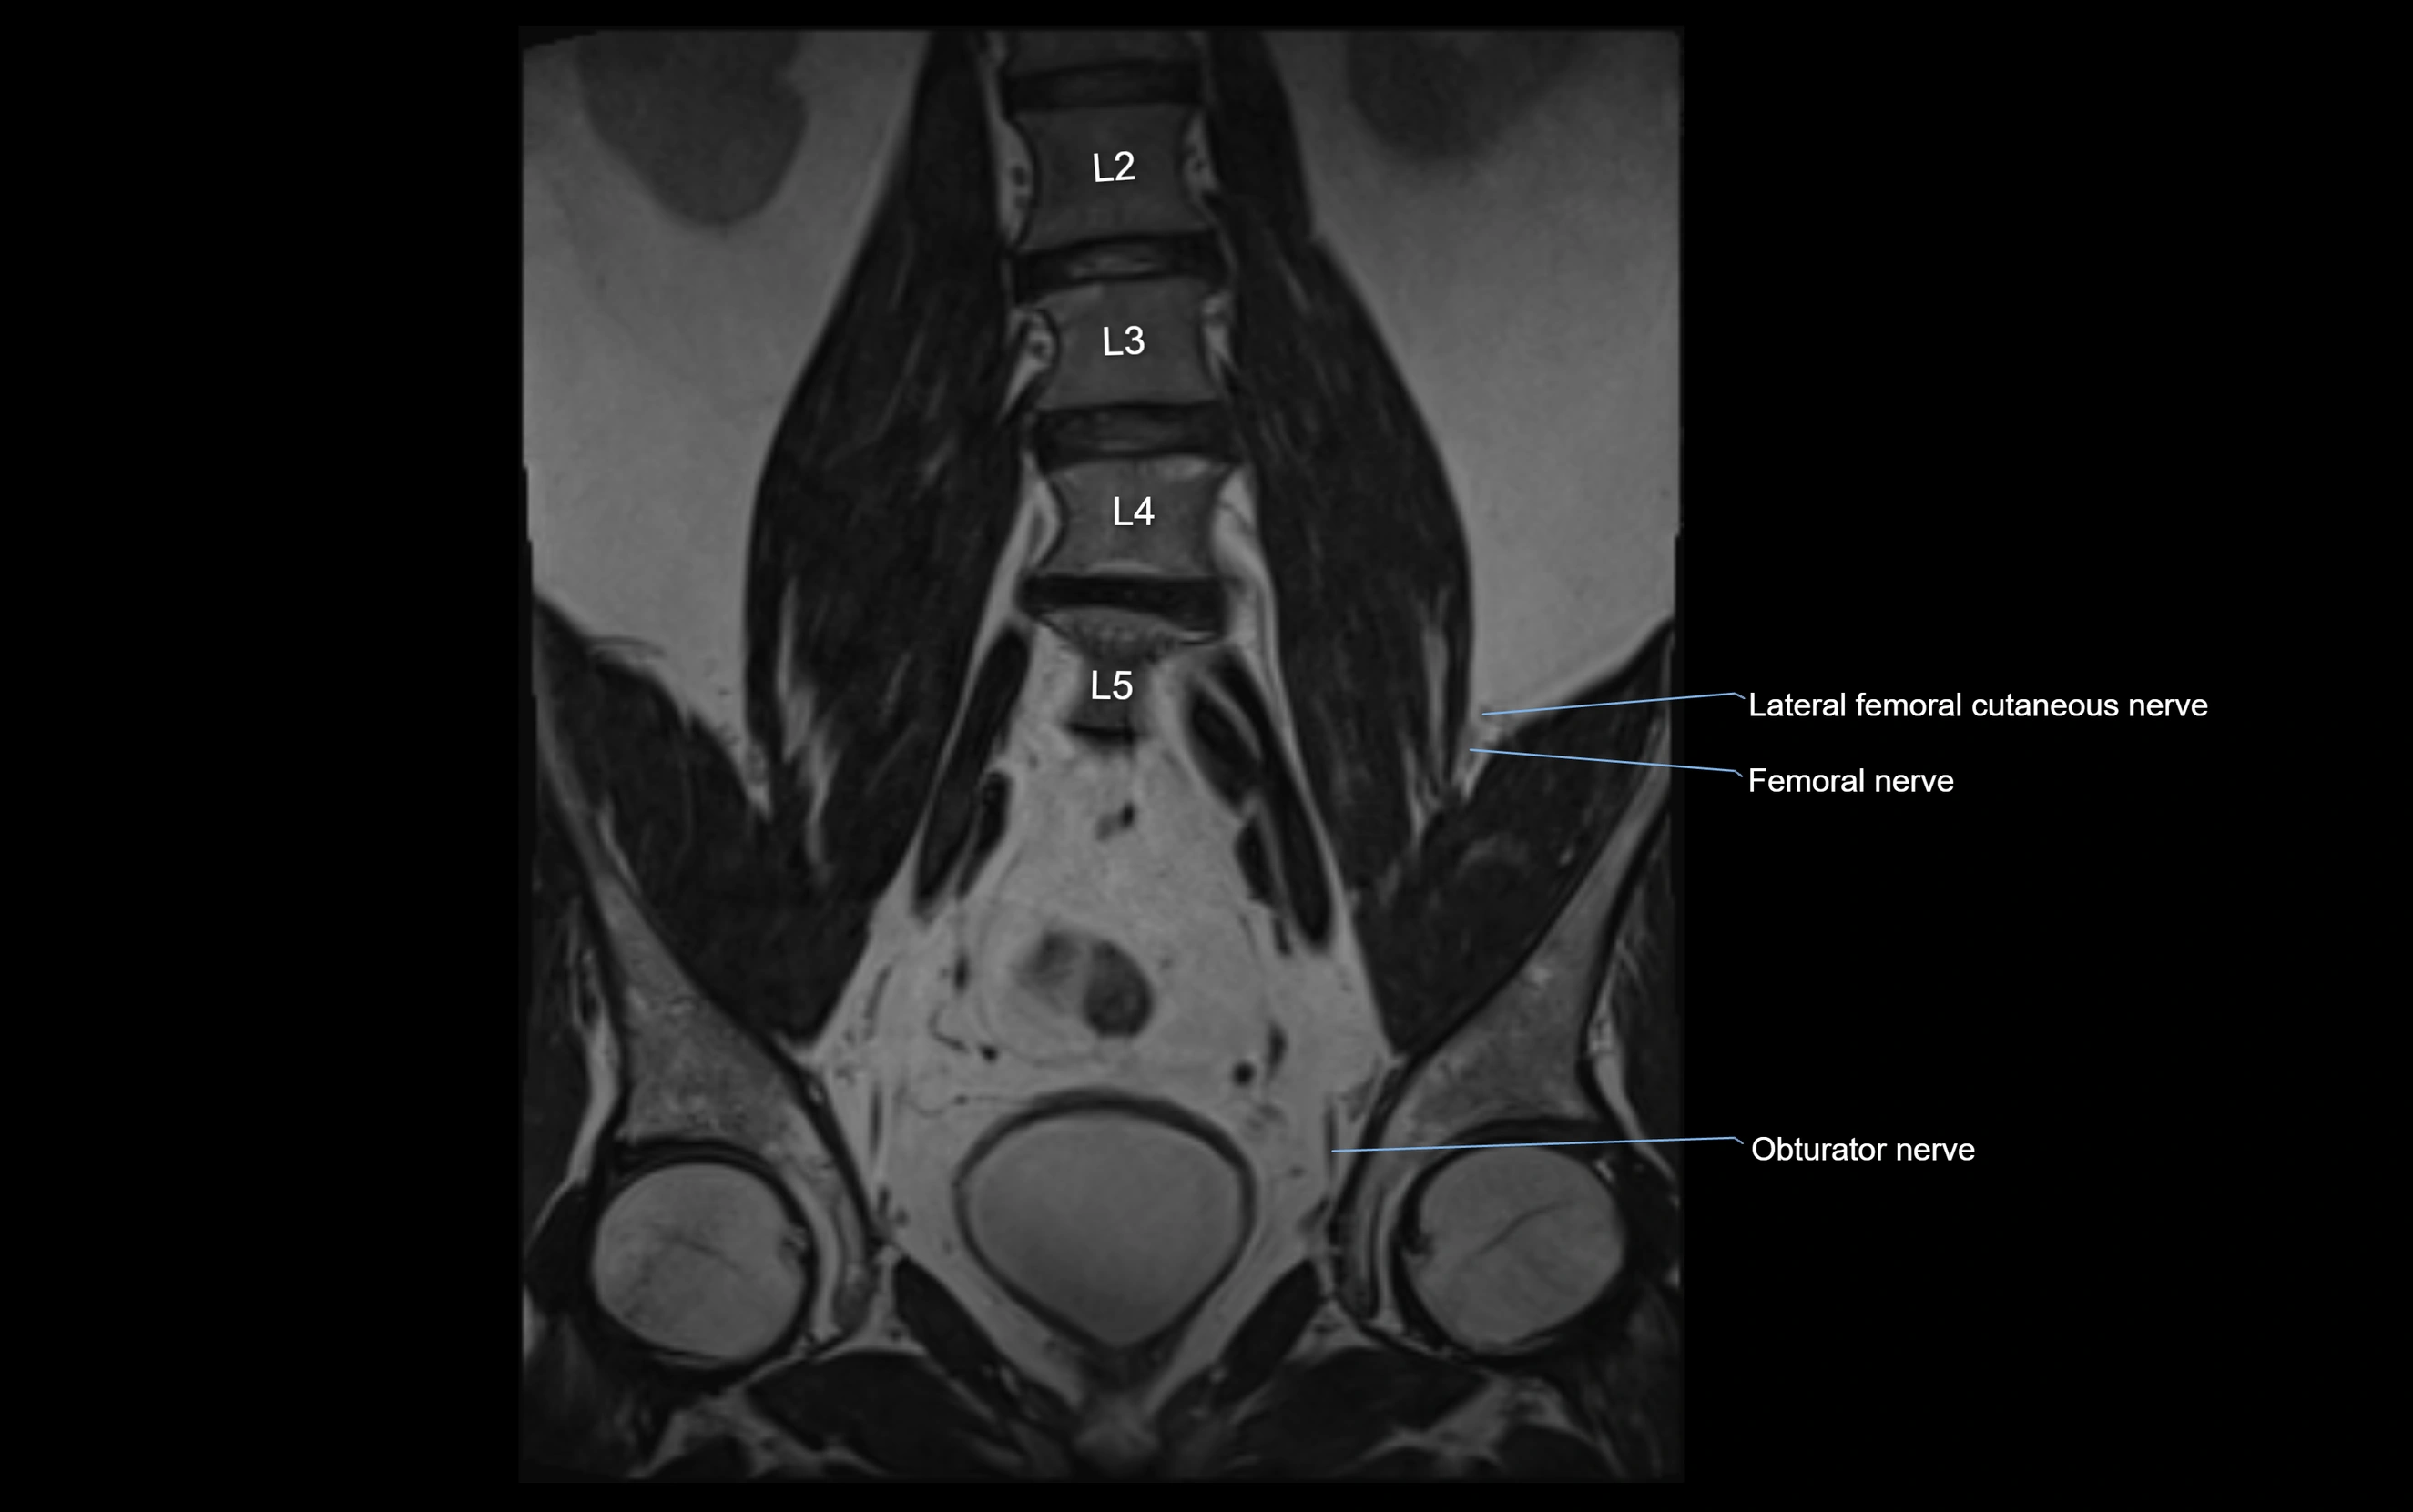

MRI image

image